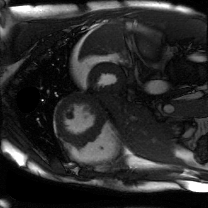

Supervised Deep-Learning (DL)-based reconstruction algorithms have shown state-of-the-art results for highly-undersampled dynamic Magnetic Resonance Imaging (MRI) reconstruction. However, the requirement of excessive high-quality ground-truth data hinders their applications due to the generalization problem. Recently, Implicit Neural Representation (INR) has appeared as a powerful DL-based tool for solving the inverse problem by characterizing the attributes of a signal as a continuous function of corresponding coordinates in an unsupervised manner. In this work, we proposed an INR-based method to improve dynamic MRI reconstruction from highly undersampled k-space data, which only takes spatiotemporal coordinates as inputs. Specifically, the proposed INR represents the dynamic MRI images as an implicit function and encodes them into neural networks. The weights of the network are learned from sparsely-acquired (k, t)-space data itself only, without external training datasets or prior images. Benefiting from the strong implicit continuity regularization of INR together with explicit regularization for low-rankness and sparsity, our proposed method outperforms the compared scan-specific methods at various acceleration factors. E.g., experiments on retrospective cardiac cine datasets show an improvement of 5.5 ~ 7.1 dB in PSNR for extremely high accelerations (up to 41.6-fold). The high-quality and inner continuity of the images provided by INR has great potential to further improve the spatiotemporal resolution of dynamic MRI, without the need of any training data.

翻译:在这项工作中,我们建议了一种基于IRI的方法,用这种方法来改进动态磁共振感应成像(MRI)重建,而该方法只是以高度低劣的 k-空间数据为基础,而该数据仅以磁共振坐标作为投入。具体地说,拟议的IRI将动态MRI图像作为一种隐含功能来表示,并将其编码到神经网络中。网络的权重仅从稀有的(k, t)空间数据本身中学习,而没有外部培训数据集或先前的图像。 利用基于IRI的强有力隐含性稳定化,同时不以清晰的动态和时空坐标坐标坐标坐标坐标作为投入。 拟议的IRIR将动态MRI图像作为一种隐含功能,将其编码到神经网络中。网络的权重仅从淡化的(k, t)空间数据本身学习,而没有外部培训数据集或先前的图像。